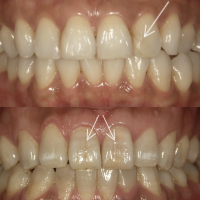

前歯のヒビの症例

症例1

治療方法 ラミネートベニア

治療期間 1ヶ月

治療費用 1歯 110,000×8本 ¥880,000(税込)

処置料金 ¥16,500

総額 ¥896,500(税込)

※治療当時の価格です

治療の副作用.リスク 歯ぎしりや食いしばりが強いと欠けることがある

ラミネートベニア

前歯のヒビと色素沈着がお悩みでした。ホワイトニングの効果がでにくい歯の質の場合は、ヒビを補強して質感を整えられるラミネートベニア法が最適です。上顎8本のラミネートベニア法で治療を行いました。元々食いしばり癖がヒビの原因になっている経緯があったため、治療後のマウスピース装着で歯を守り、ボトックス注入で咬合力コントロールを行っています。